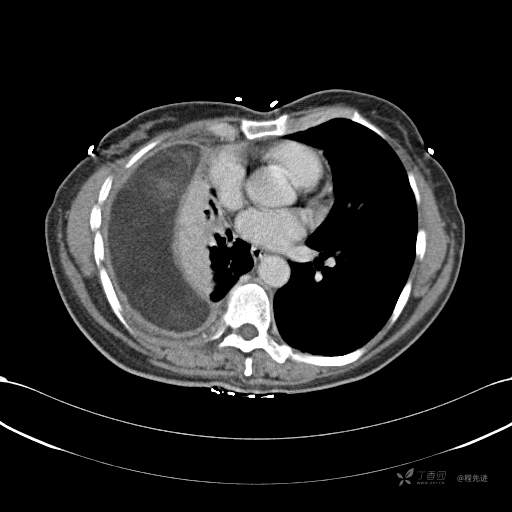

患者性别:女

患者年龄:51岁

简要病史:胸闷半年